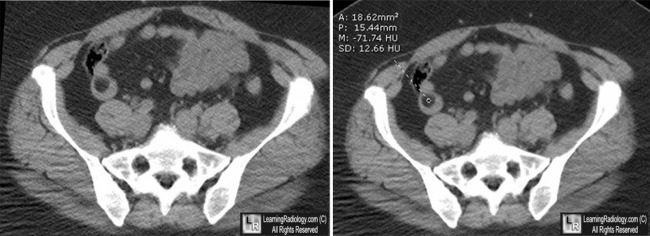

- CT will show a low density mass in the wall of the small bowel

- Homogeneous mass with Hounsfield units between −80 and –120

Lipoma of Small Bowel. The white arrow points to sharply marginated filling defect in the distal small bowel. The mass measures -71 Hounsfield units, consistent with fat density.